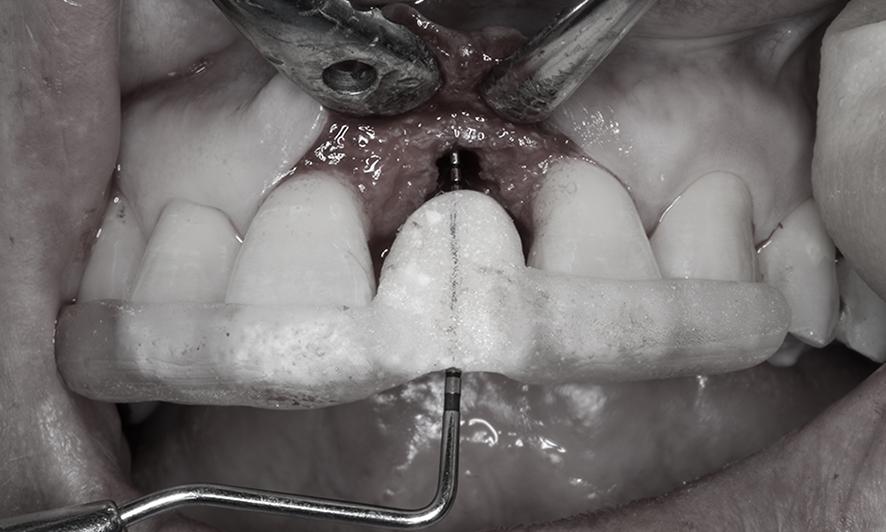

手術では、事前シミュレーションで決定した理想的な位置にインプラントを埋入するため、「埋入ガイド(ステント)」を用いて精密に処置を行いました。さらに、歯ぐきを慎重に剥離し、必要な厚さを盛り足して縫合しました。

シミュレーション通りの位置にインプラントを埋入出来るようにステントと呼ばれる(透明な樹脂の部分)埋入ガイドを使い、正確性と安全性を確保しています。

インプラント埋入と同時に結合組織移植術のために、部分層弁という手法で一部の歯茎を慎重に剥がします。